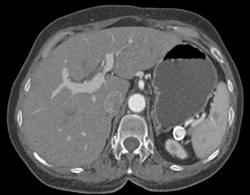

Splenic Artery Aneurysm